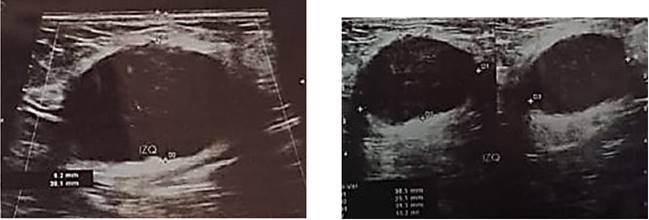

Estos hallazgos fueron consistentes con el proceso infeccioso localizado en región inguinal. La persistencia de estas alteraciones más la evolución desfavorable del paciente evidenciada por la secreción purulenta continua a través del drenaje tipo Penrose, motivó la realización de una ecografía de partes blandas que arrojó los siguientes hallazgos (Figura 1):

La evolución posterior fue también desfavorable, presentando diversas complicaciones, siendo la principal un marcado desequilibrio electrolítico que persistió a pesar del tratamiento y constantes reposiciones (Tabla 2). Esta evolución atípica llevó a realizar estudios más exhaustivos, incluyendo tomografías abdominopélvicas que revelarían posteriormente la verdadera extensión y naturaleza de la patología.